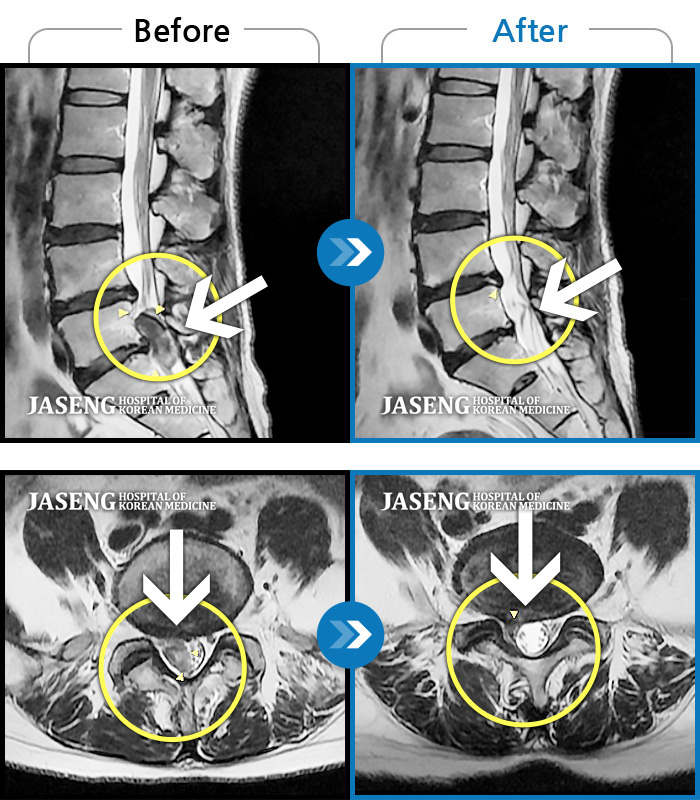

허리디스크

해운대 · 이상건 원장

허리통증 및 우측 하지 저림과 근력 저하

촬영시기

2018.02.05 ~ 2018.08.25

2019.01.04

조회수 5,050